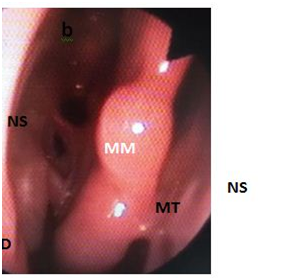

Figure 3B Conchopexy suture - Postoperative bilateral endoscopic view 1year after.

(MT: Middle Turbinate; MM: Middle Meatus; NS: Nasal Septum; N: Needle)

The needle is introduced into the left nasal cavity oriented vertically, visualized with a 0˚ nasal telescope, and passed through the head of the middle turbinate, septum and the contralateral middle turbinate in a single pass. It is then brought back to the right middle turbinate and passed through the septum to the initial side to be knotted with direct visualization. This technique has been criticized for its likely effect on olfaction but there are studies which confirm that it does not impair the function of olfaction.3 Endoscopic Conchopexy Suture has also been considered a difficult technical and lengthens the operating time due to the need to tie inside the nasal cavity, but a new technique has simplified this process of suture to avoid knot-tying within the nasal cavity using a monofilament barbed suture with knot tied.1 This technique is mainly indicated to cases of Endoscopic Surgery with an unstable middle turbinate and also if a septoplasty ES performed. In these cases the Bolgerization technique can produce major injure of the middle turbinate and a septal perforation, hence it is preferred to perform a conchopexy suture avoiding these complications. Moreover, Conchopexy Suture is more comfortable for patients because it needs no postoperative removable nasal packing.